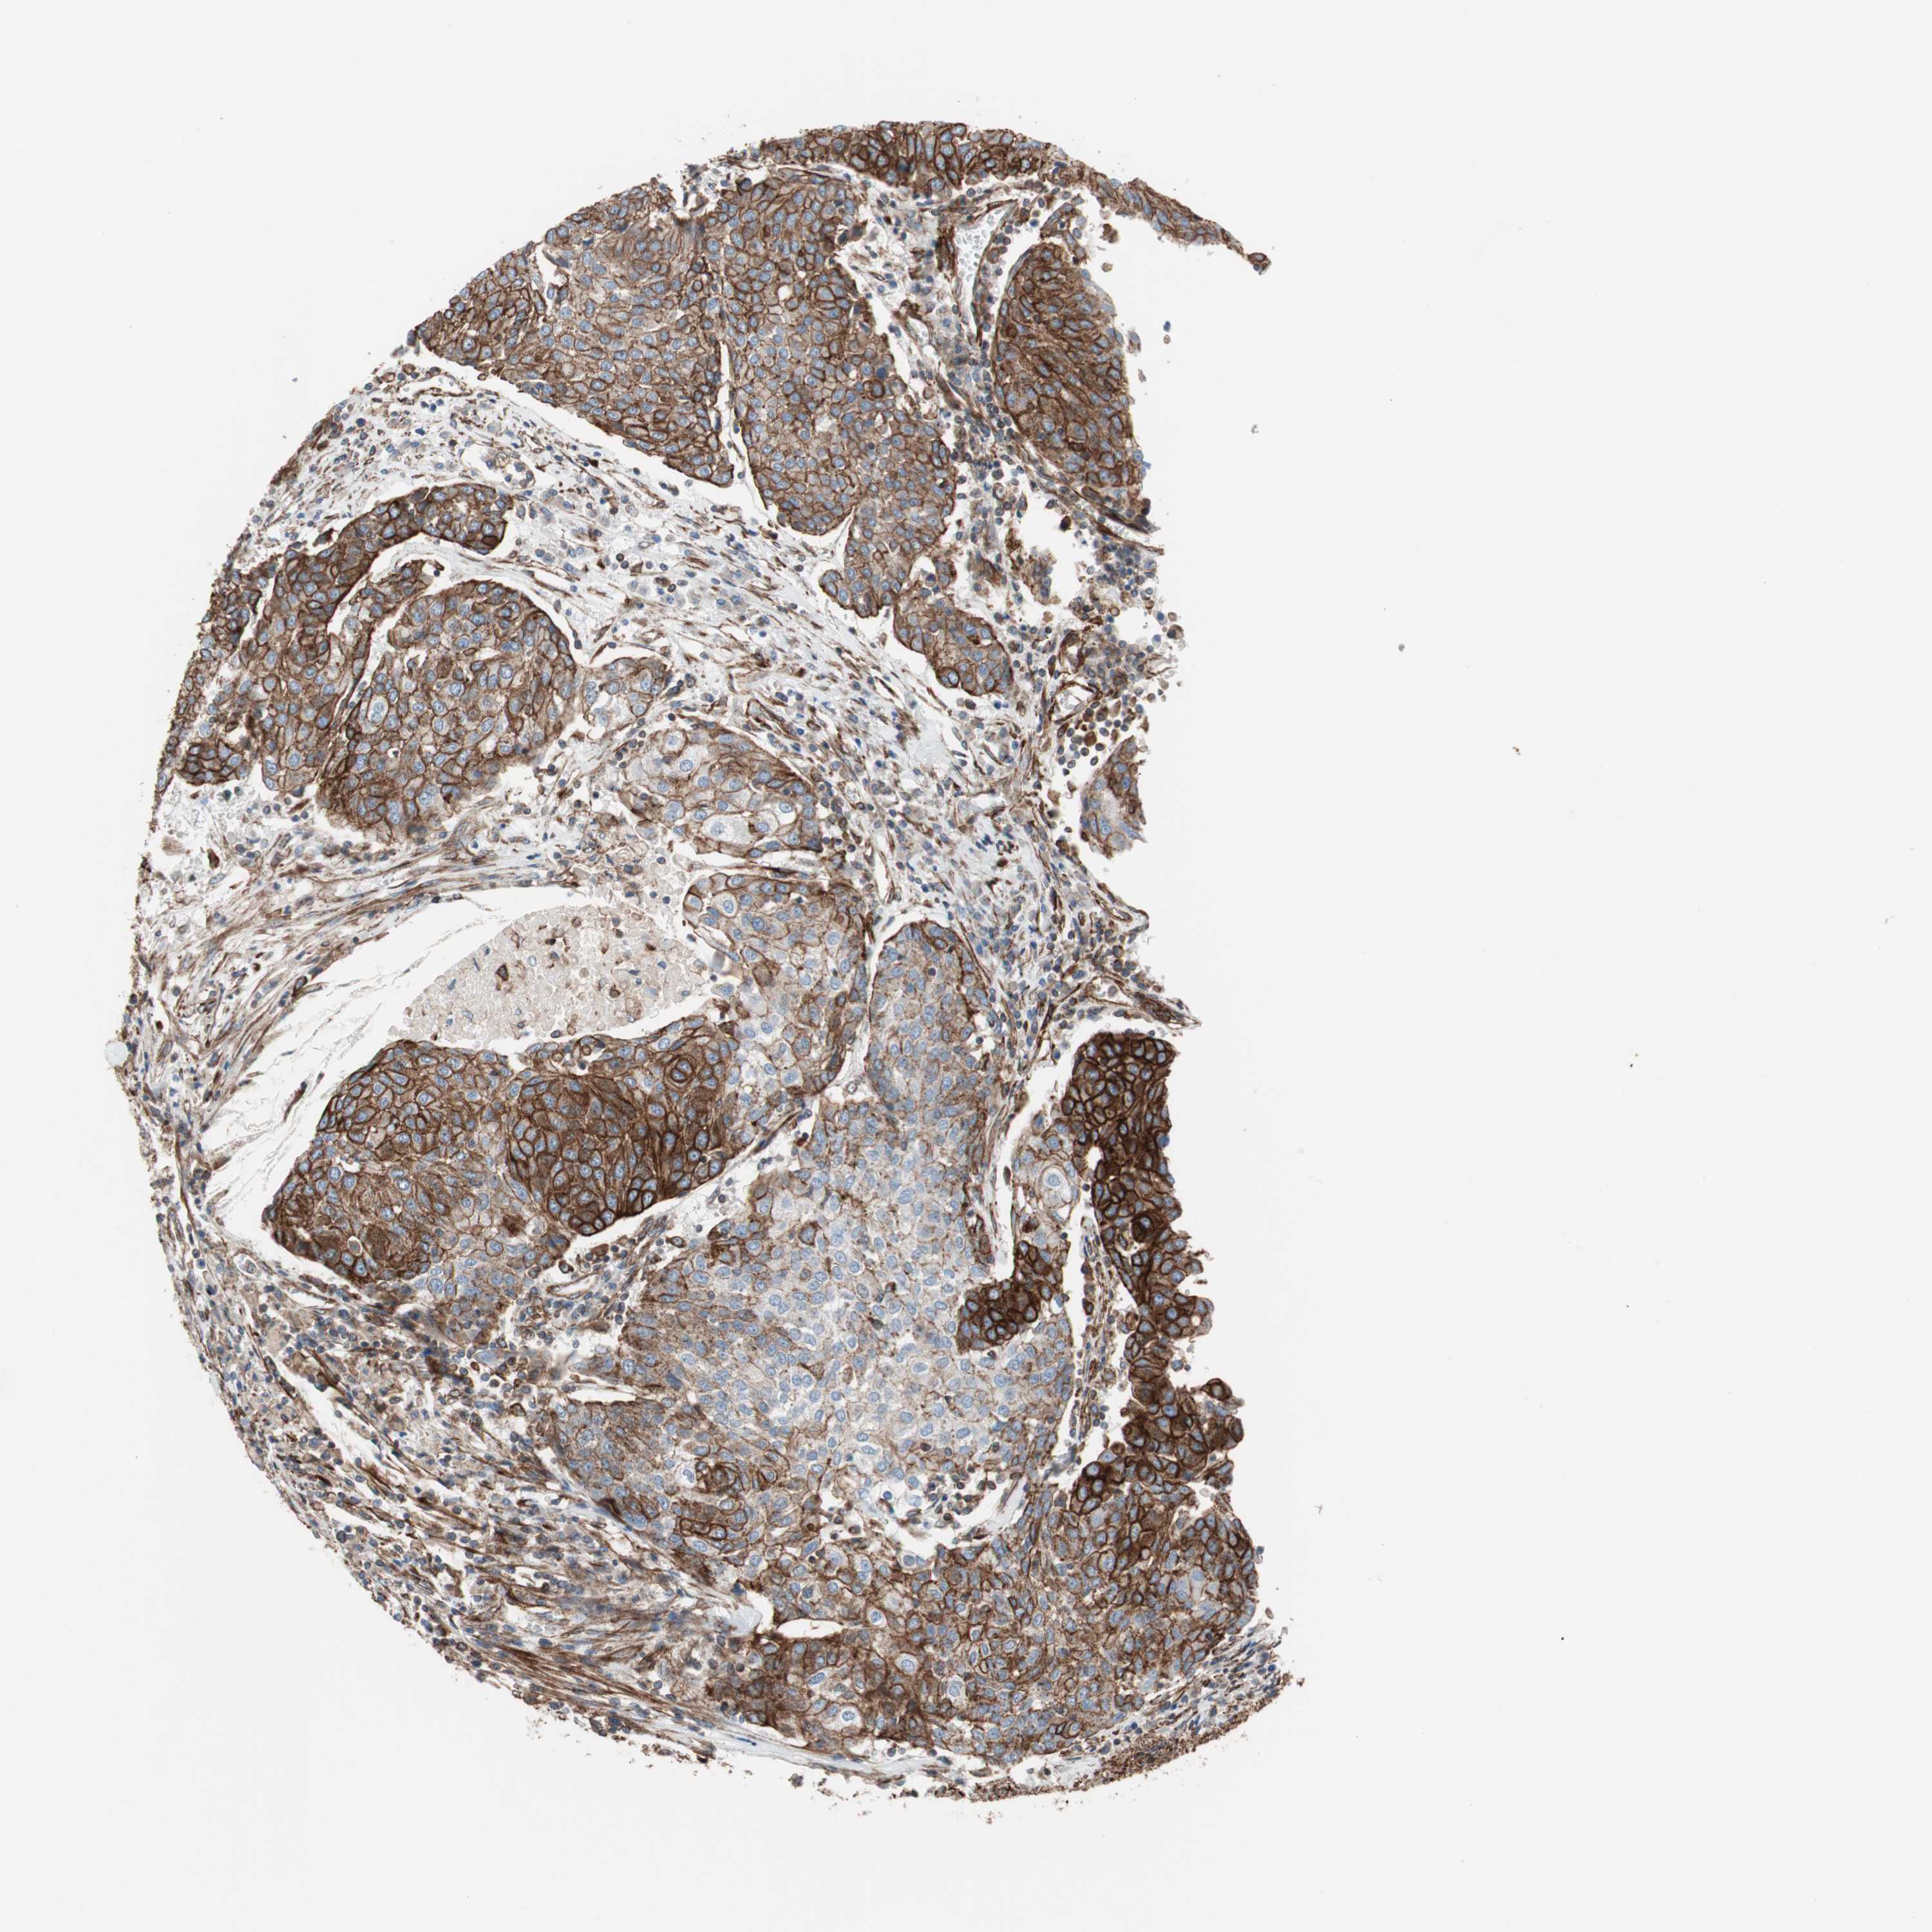

UROTHELIAL CANCER - Protein expressioni

A mouse-over function shows sample information and annotation data. Click on an image to view it in a full screen mode. Samples can be filtered based on level of antibody staining by selecting one or several of the following categories: high, medium, low and not detected. The assay and annotation is described here.

Antibody stainingi

Antibody staining in the annotated cell types in the current human tissue is reported as not detected, low, medium, or high, based on conventional immunohistochemistry profiling in selected tissues. This score is based on the combination of the staining intensity and fraction of stained cells.

Each image is clickable and will lead to virtual microscopy that enables deeper exploration of all samples and also displays staining intensity scores, fraction scores and subcellular localization as well as patient and tissue information for each sample.

Antibody HPA007342

Staining

High

Medium

Low

Not detected

Intensity

Strong

Moderate

Weak

Negative

Quantity

>75%

75%-25%

<25%

None

Location

Nuclear

Cytoplasmic/membranous

Cytoplasmic/membranous,nuclear

Urothelial carcinoma, High grade